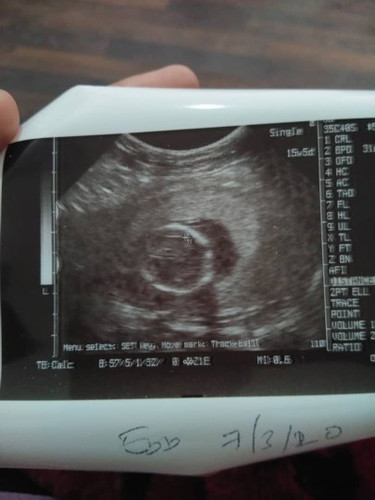

Anak sya bru usia 15 mingu..tpi da sonsang..apa kh bahaya ataw tk

Baca lagiBelum boleh dikatakan songsang sbb awal lagi. Baby still active bergerak. Memang mcm tu pun klau awal2 ni. Bukan songsang tau sis.. Just normal.. Lain la klau nk almost 37 still mcm tu. Head not engage.. Itu pun doc akan try pusingkan. Klau bby still x turn baru doc recommend Cs.

Awl lg sis br 15mggu kan.jgn stress2 k..... Andai kata smpai mggu ke 34 or 35 n smpai due la katakan xjuge berubah still sm.... Jgn risau..doc akn buat ecv pusingkn bby pd tmpt yg spttnye sblm kita due... 😉✌

sy baru je scan utk 19weeks tadi ..n doktor kata sonsang tp bby mmg akan pusing2 lagi ..so xde yg nk drisaukan ..kecuali kalau dh 7months ke atas